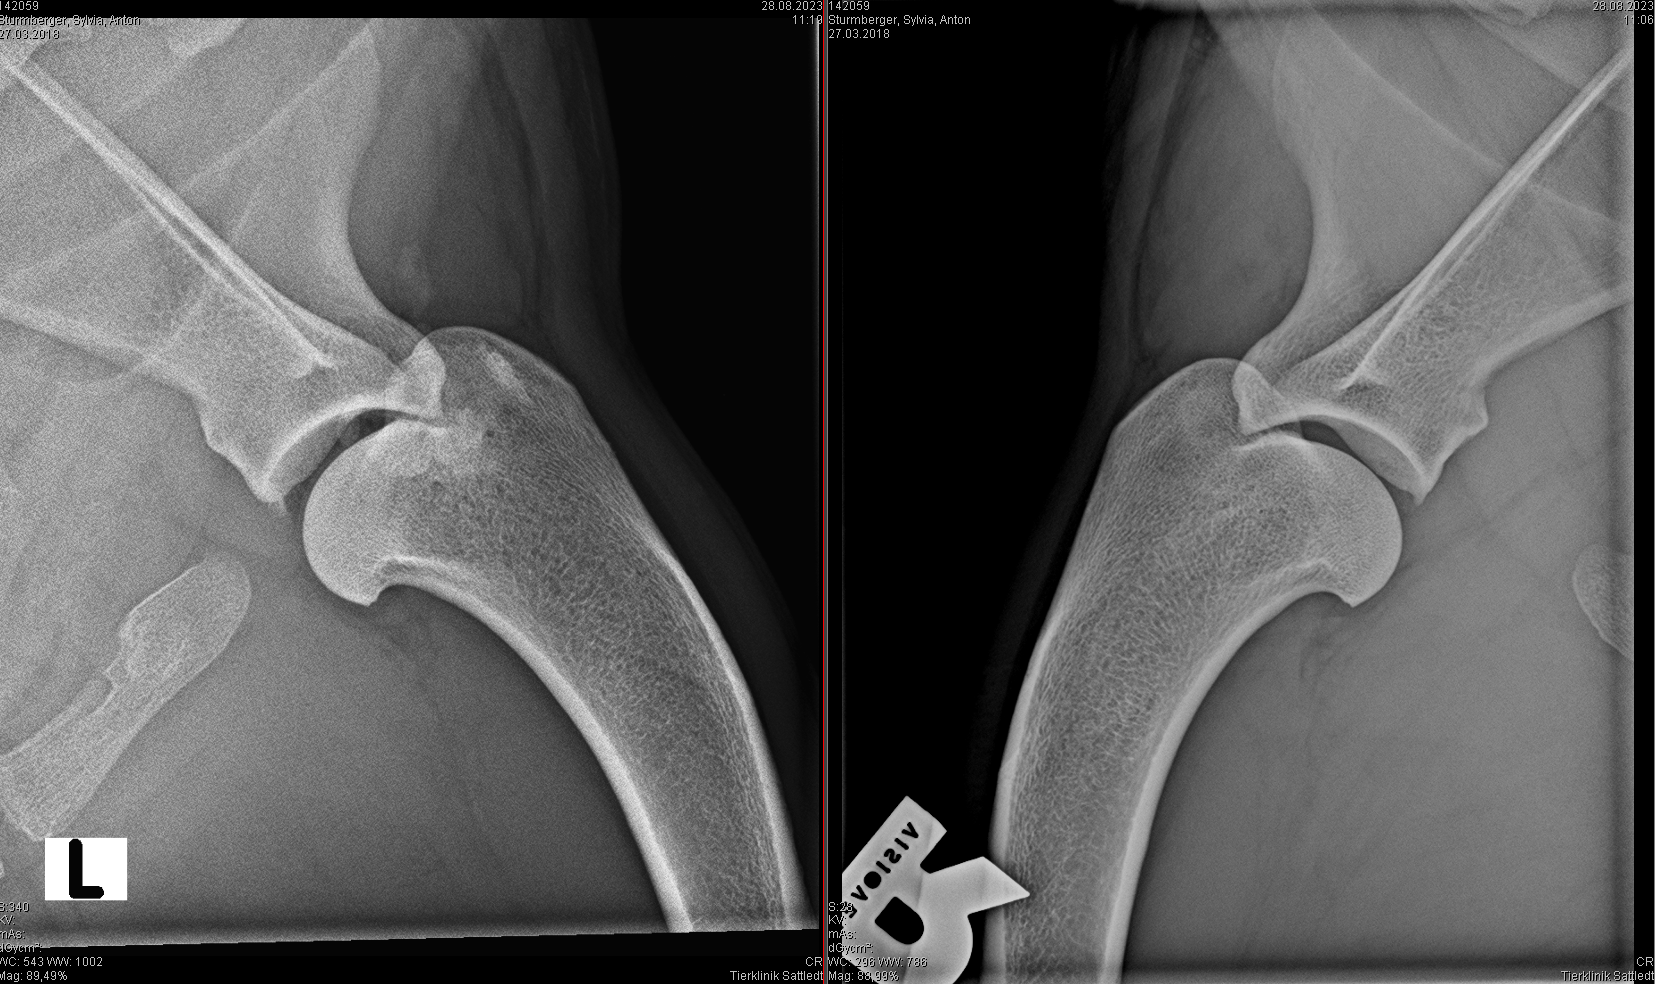

Insertionstendinopathie M. infraspinatus

- Druckschmerz auf Ansatz M. infraspinatus (Muskelansatz am Tub. minus humeri - Bursa zw. Infraspinatussehne und Humerus)

- OP: Chirurgische Resektion der Sehne und Bursa des M. infraspinatus mit / ohne Reinsertion der Endsehne

- McKee WM, et al (2007): Ossification of the infraspinatus tendon-bursa in 13 dogs. The veterinary record 29.